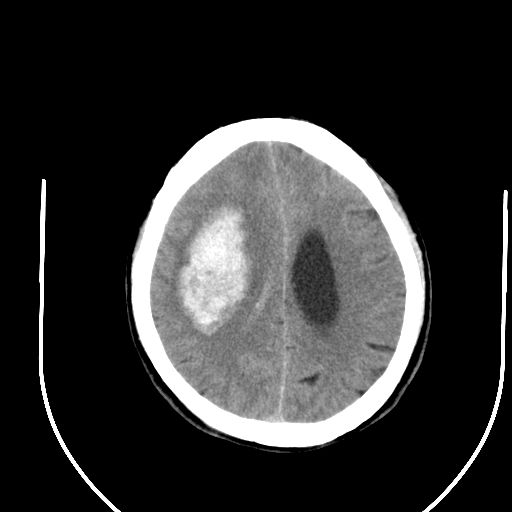

标题: CT24997:M,60Y,突发昏迷30分钟,有高血压病史。 [打印本页]

标题: CT24997:M,60Y,突发昏迷30分钟,有高血压病史。

右侧基底节区脑出血并破溃入脑室。

支持楼主诊断,脑中线结构有偏移,脑疝形成可能!

1右侧基底节脑出血伴脑干出血并破入脑室系统脑疝形成2梗阻性脑积水

1)右侧基底节脑出血伴脑干出血并破入脑室系统。2)大脑镰下疝。3)梗阻性脑积水。

1、右侧基底节脑出血伴脑干出血并破入脑室系统。

2、大脑镰下疝。

3、梗阻性脑积水。